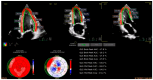

Cardiovascular diseases and cancer are the leading causes of morbidity and mortality in modern society. Expanding cancer therapies that have improved prognosis may also be associated with cardiotoxicity, and extended life span after survivorship is associated with the increasing prevalence of cardiovascular disease. As such, the field of cardio-oncology has been rapidly expanding, with an aim to identify cardiotoxicity and cardiac disease early in a patient who is receiving treatment for cancer or is in survivorship. Artificial intelligence is revolutionizing modern medicine with its ability to identify cardiac disease early. This article comprehensively reviews applications of artificial intelligence specifically applied to electrocardiograms, echocardiography, cardiac magnetic resonance imaging, and nuclear imaging to predict cardiac toxicity in the setting of cancer therapies, with a view to reduce early complications and cardiac side effects from cancer therapies such as chemotherapy, radiation therapy, or immunotherapy.